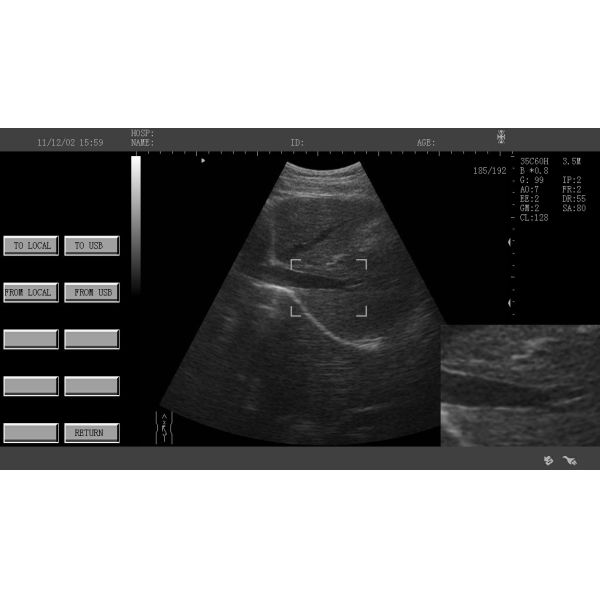

Imágenes